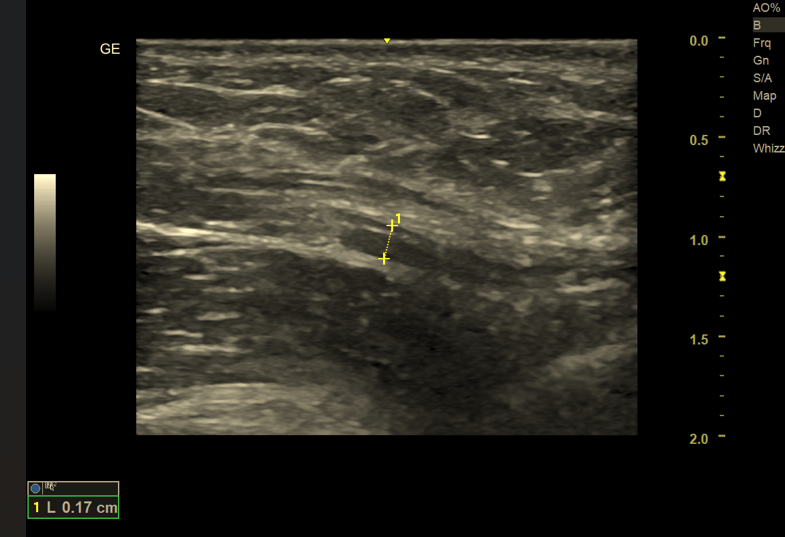

2. Zaburzenia echostruktury nerwu

Prawidłowy nerw obwodowy w badaniu USG charakteryzuje się regularną, pęczkową echostrukturą, przypominającą obraz „plastra miodu” w przekroju poprzecznym oraz równoległe pasma w przekroju podłużnym.

Zmiany patologiczne obejmują:

• utratę wyraźnego podziału na pęczki nerwowe,

• obniżenie echogeniczności (hipoechogeniczność),

• niejednorodność struktury wewnętrznej.

Tego typu obraz może świadczyć o obrzęku nerwu, procesie zapalnym, przewlekłym ucisku lub degeneracji włókien nerwowych. Ocena echostruktury ma szczególne znaczenie w różnicowaniu zmian ostrych i przewlekłych.